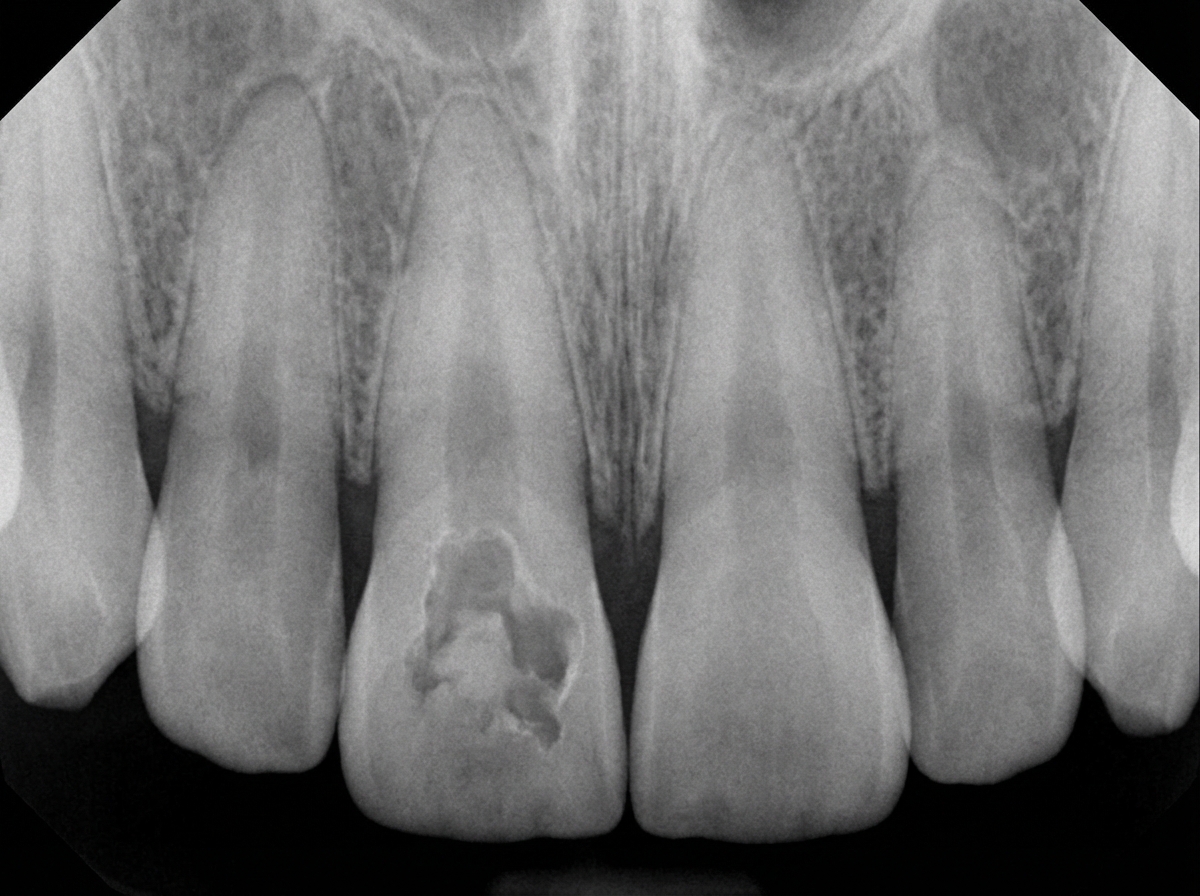

A patient gives a history of previous chronic abscess on the deciduous precursor of tooth 11. The following radiograph indicates:

Explanation: ***Turner's hypoplasia*** - **Localized enamel hypoplasia** of a permanent tooth caused by **infection or trauma** to the overlying deciduous tooth, exactly matching this patient's history of chronic abscess. - Presents as **irregular enamel surface** with **yellowish-brown discoloration** and **pitted areas** on the crown, typically affecting only one tooth. *Enamel hypoplasia* - This is a **generalized condition** affecting multiple teeth due to **systemic factors** during tooth development. - Does not explain the **localized involvement** of tooth 11 following a specific history of deciduous tooth infection. *Amelogenesis imperfecta* - A **genetic disorder** affecting **enamel formation** in all teeth, not just a single tooth. - Would show **bilateral symmetrical involvement** and **family history**, which contradicts the localized presentation here. *Dentinogenesis imperfecta* - A **genetic defect** affecting **dentin formation**, causing **opalescent teeth** with **amber or blue-gray discoloration**. - Affects the **dentin layer**, not enamel, and would involve **multiple teeth** rather than a single localized defect.